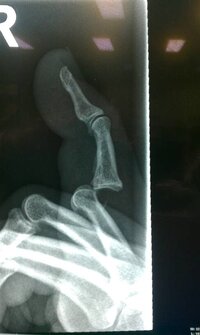

Blade said:I have this really cool stainless steel pin in my finger. It is supposed to hold it all together but it is really uncomfortable. It has been in almost a week and I fear it has to be in allot longer.

I have already missed a 3 day golf trip with my friends and who knows what else in the next while.